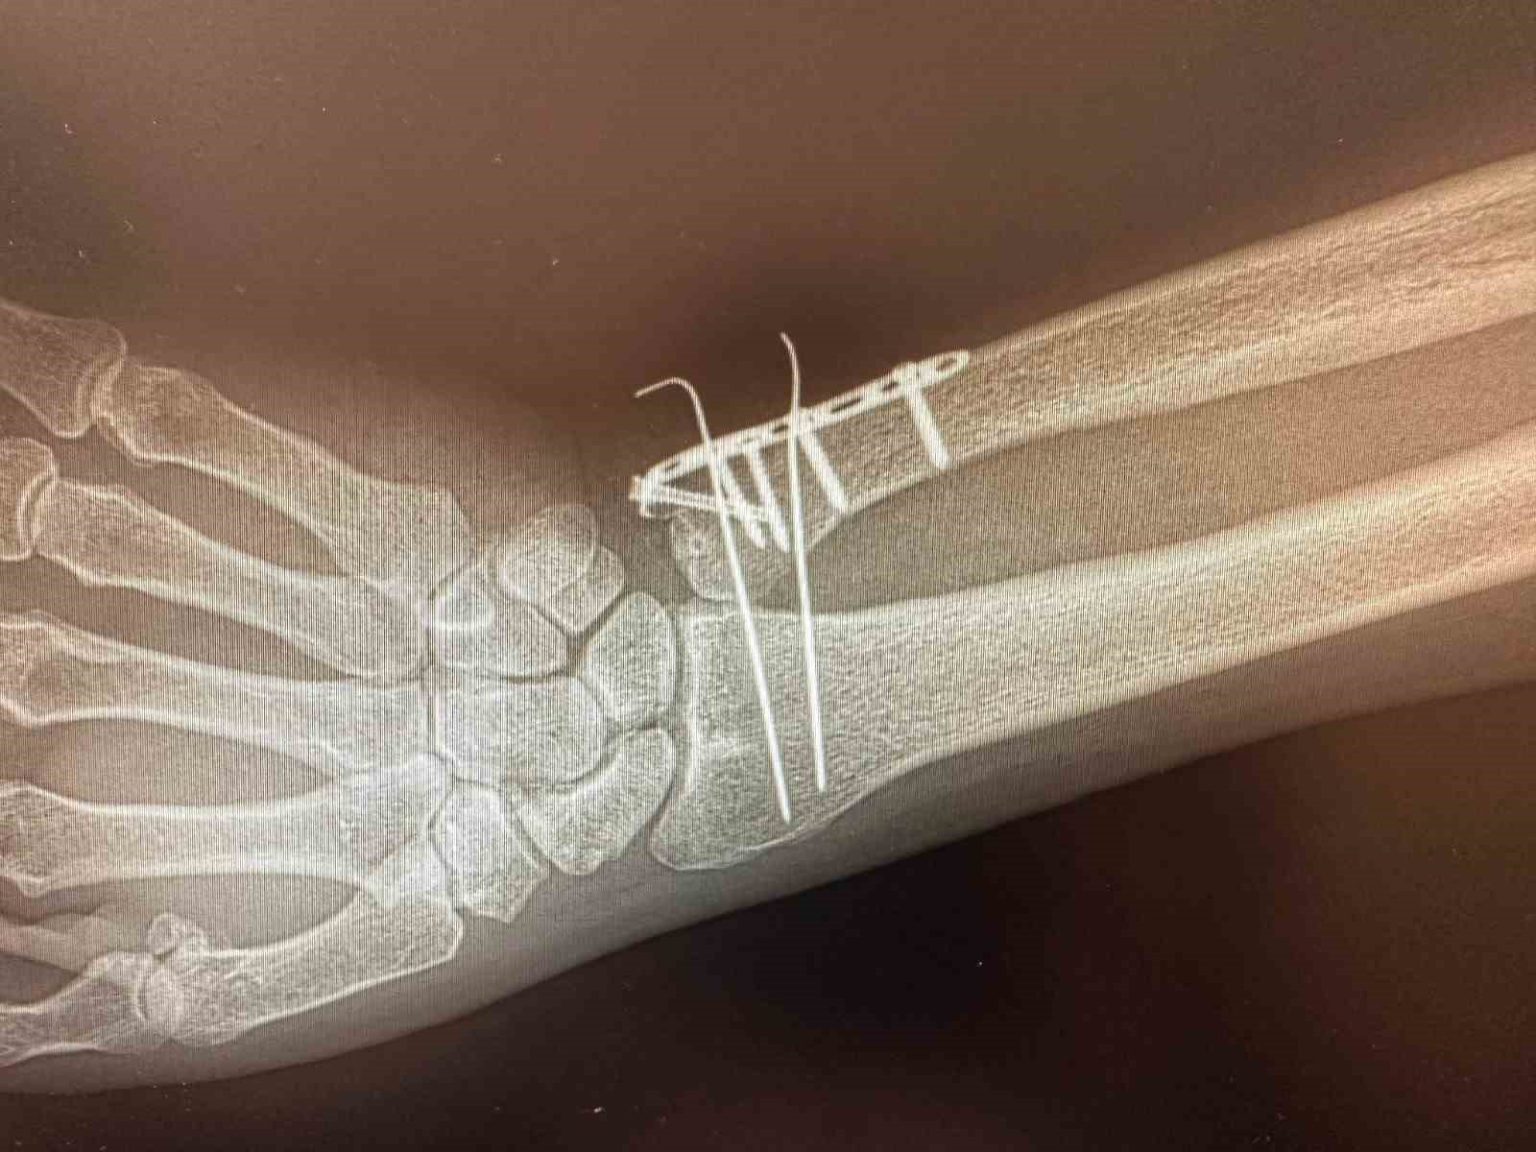

Cihazın özellikle kırıkların düzeltilmesi, vida ve plak uygulamaları, kalça ve diz protez ameliyatları gibi ortopedi ve travmatoloji işlemlerinde etkin şekilde kullanılacağı ifade edildi.